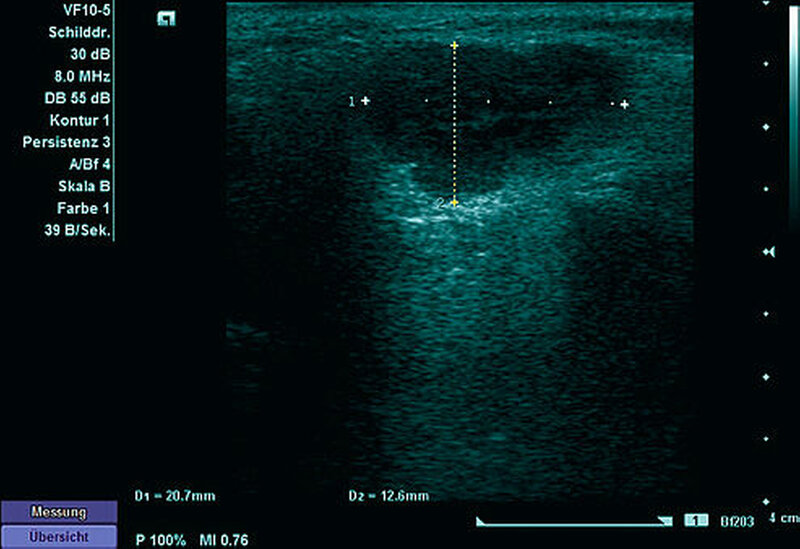

Zur weiteren Diagnostik erfolgte eine Sonografie (Abbildung 2) sowie eine drei- dimensionale Bildgebung mittels MRT (Abbildung 3). Hier zeigte sich eine Formation in der linken Glandula parotis ohne Infiltration der Nachbarstrukturen, die bildmorphologisch am ehesten einem pleomorphen Adenom entsprach.